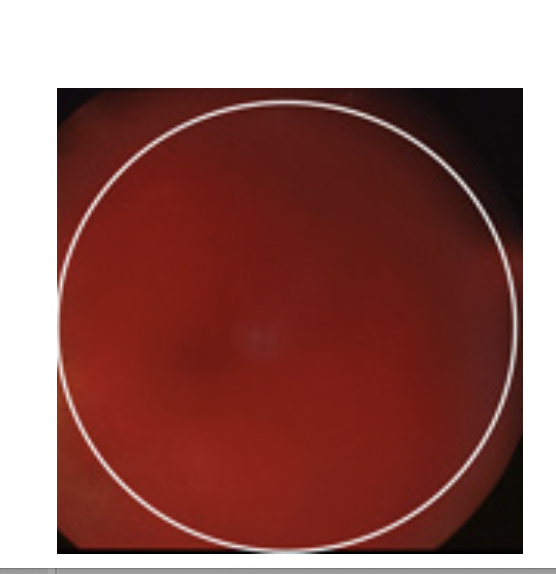

Du foretager en objektiv undersøgelse og finder følgende:

Visus på højre øje: lyssans med projektion

Visus på venstre øje: 1,0 (6/6) med egen korrektion

ESLM: Normal

Pupiller: Runde og egale med naturlig reaktion for direkte og indirekte lys.

Synsfelt for hånd på højre øje: kan ikke undersøges

Synsfelt for hånd på venstre øje: normalt

Øjentryk: 14 mmHg på begge øjne.

Spaltelampeundersøgelse ou: Bulbi blege, corneae klare og blanke, forreste kamre af normal

dybde, irides naturlige, lentes alderssvarende.

Oftalmoskopi af højre øje: Se foto.

Oftalmoskopi af venstre øje: Normal.

Hvad er din tentative diagnose?